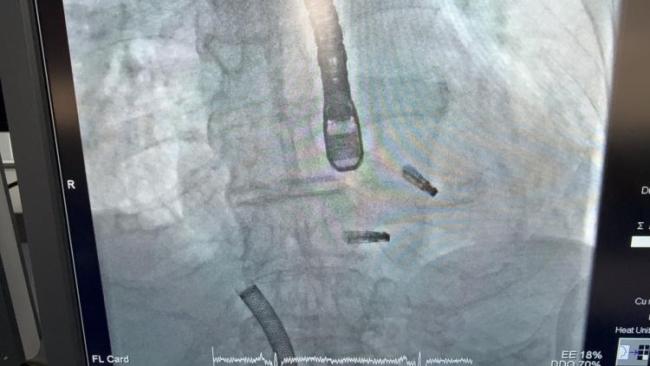

84岁老人心梗后双“心门”反流 微创手术创奇迹

心脏里两扇重要的“大门”——二尖瓣和三尖瓣——同时严重损坏,血液倒流,心脏面临崩溃